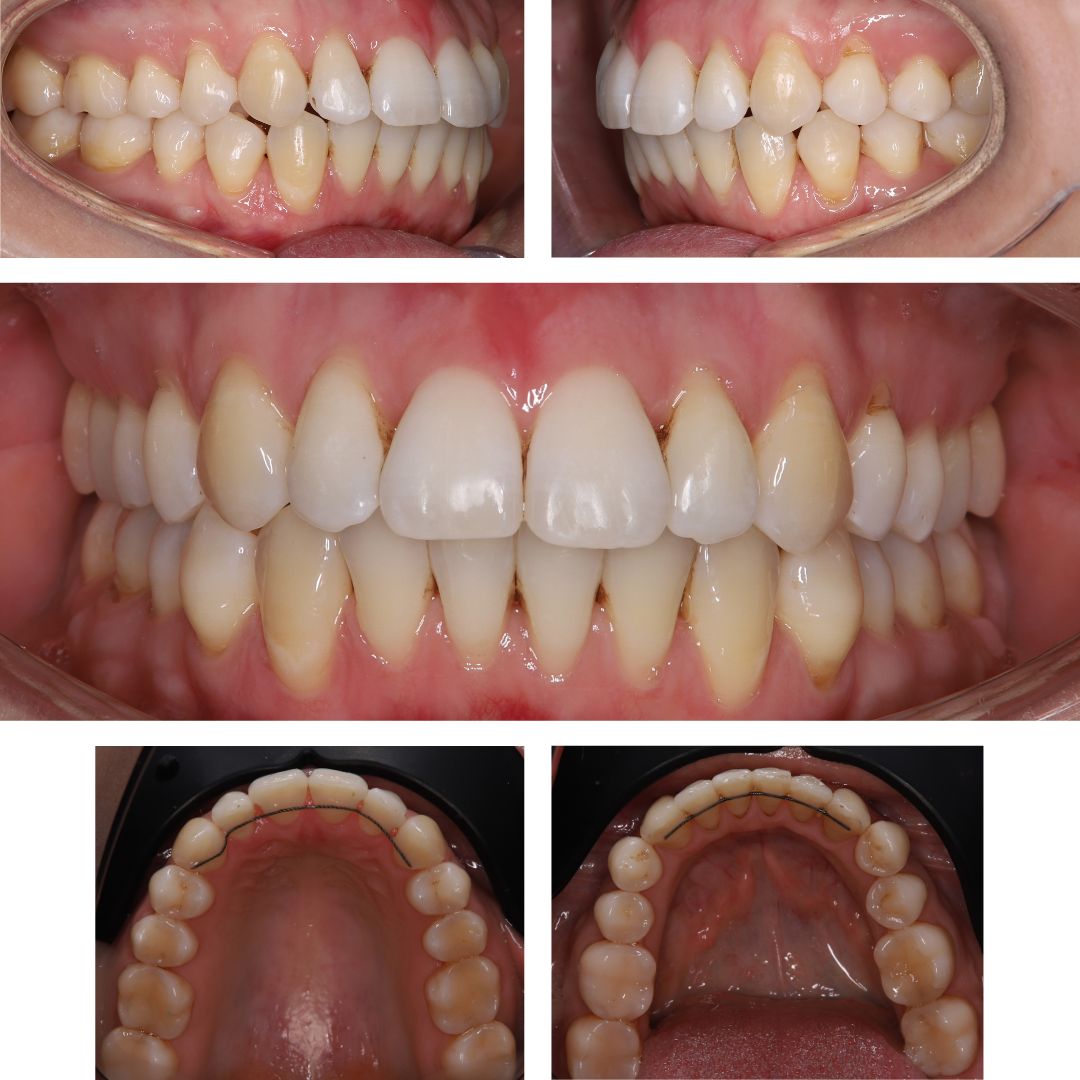

Пациентка обратилась в клинику «Норд Дентал» с запросом на улучшение эстетики улыбки.

Обследование показало:

- Сильную скученность зубов

- Дефицит места для постановки зубов в ровный ряд

- Наличии тонкого биотипа десны

ЧЕРЕЗ 2 ГОДА ЛЕЧЕНИЯ – у пациентки ровный, красивый зубной ряд с плотными межзубными контактами 🥰